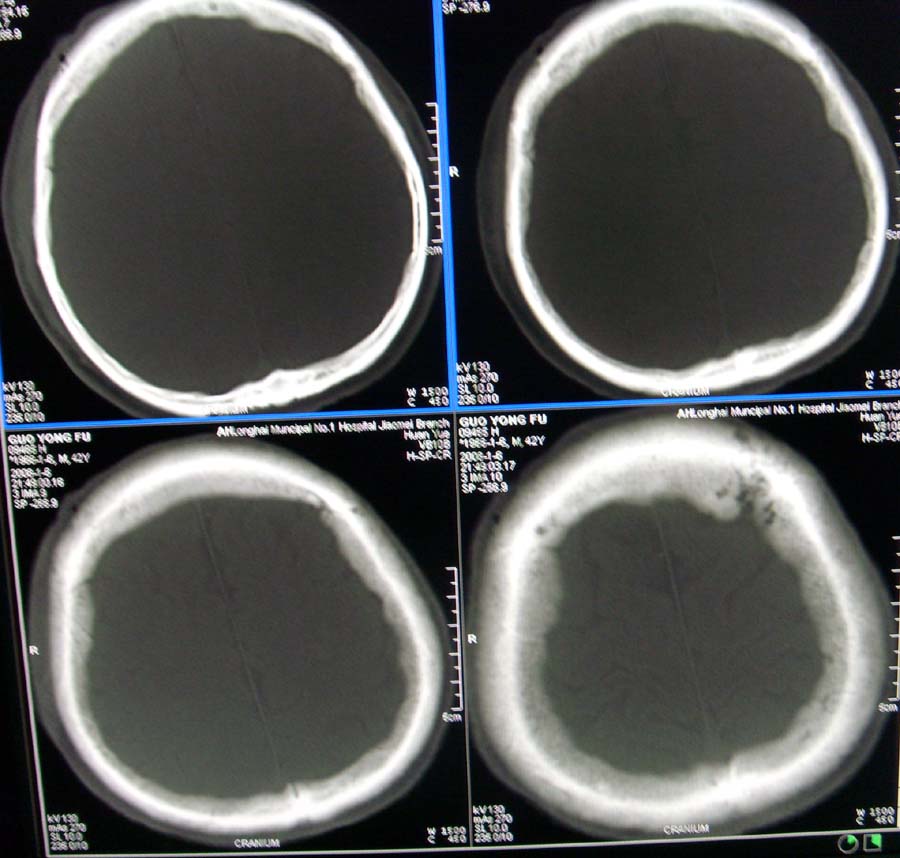

男,45,外伤体检,请问骨窗最后一层板障内低密度影是正常吗

蛛网膜颗粒压迹.

蛛网膜颗粒压迹。

蛛网膜颗粒压迹,为正常表现。